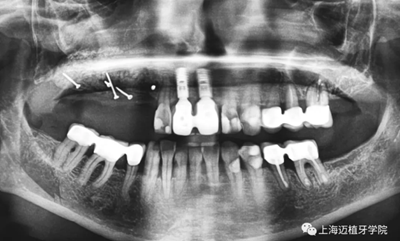

植體取出后,可以清晰地看到骨粉未成骨,還是顆粒狀

利用BBA植骨法,骨片固定頰舌側(cè)距離

中間填充自體骨屑

用骨釘固定骨板

四個月后成骨